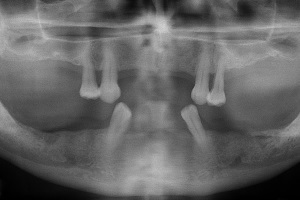

La radio panoramique d’avant traitement montre qu’il reste deux molaires au maxillaire et 8 dents à la mandibule dont 5 dents dévitalisées et deux incisives centrales légèrement mobiles . La prothèse amovible du bas ne satisfait pas non plus la patiente et la hauteur osseuse au-dessus du nerf dentaire inférieur est relativement faible des deux côtés pour poser des implants favorablement dans les secteurs postérieurs. Au maxillaire, les sini maxillaires devront être comblés pour recevoir des implants dans les secteurs postérieurs.